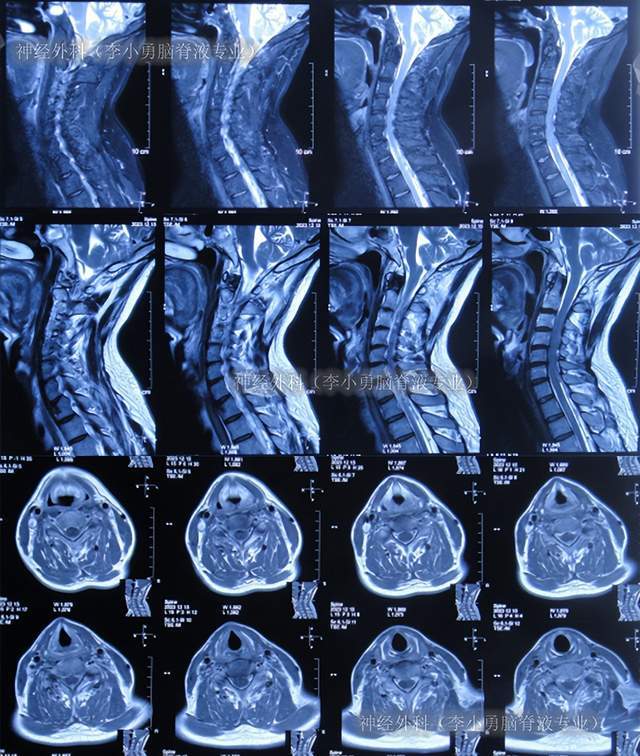

查头颅ct未见明显异常(图-1);次日再查头颅核磁,颈椎核磁(图-2,图-3)

图-29:出院时头颅核磁图-30:出院时颈髓核磁三,出院后随访出院后4个月

图-33:2023年12月18日颈髓核磁出院后8个月即2024年1月,来院复查:身体